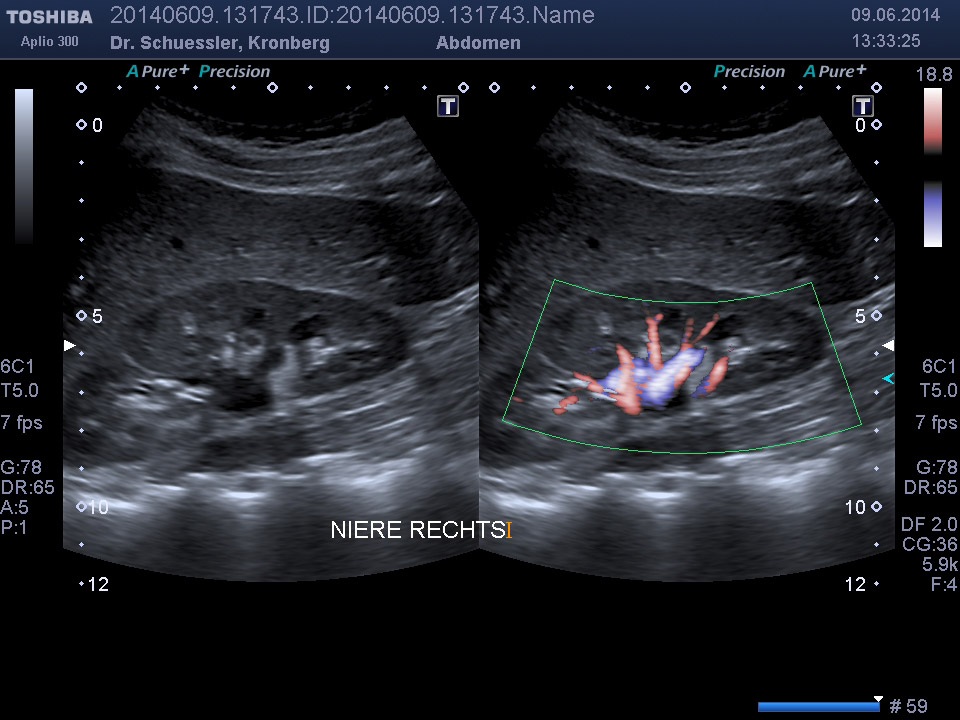

Ultraschalluntersuchung der Bauchorgane

Die Bauchultraschalluntersuchung ist das wichtigste Verfahren zur Beurteilung der gesamten Bauchorgane. Sämtliche Bauchorgane sind dem Ultraschallverfahren ohne Belastung für den Patienten gut zugängig.

Durch Ergänzung des farbkodierten Duplexverfahrens läßt sich die Durchblutungssituation der Bauchorgane erfassen.